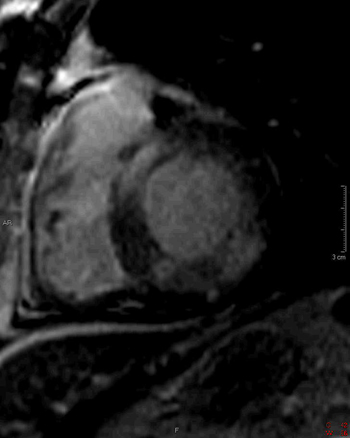

2) This inversion recovery sequence was taken 10 minutes after the administration of IV gadolinium. Which of the following entities does it show?